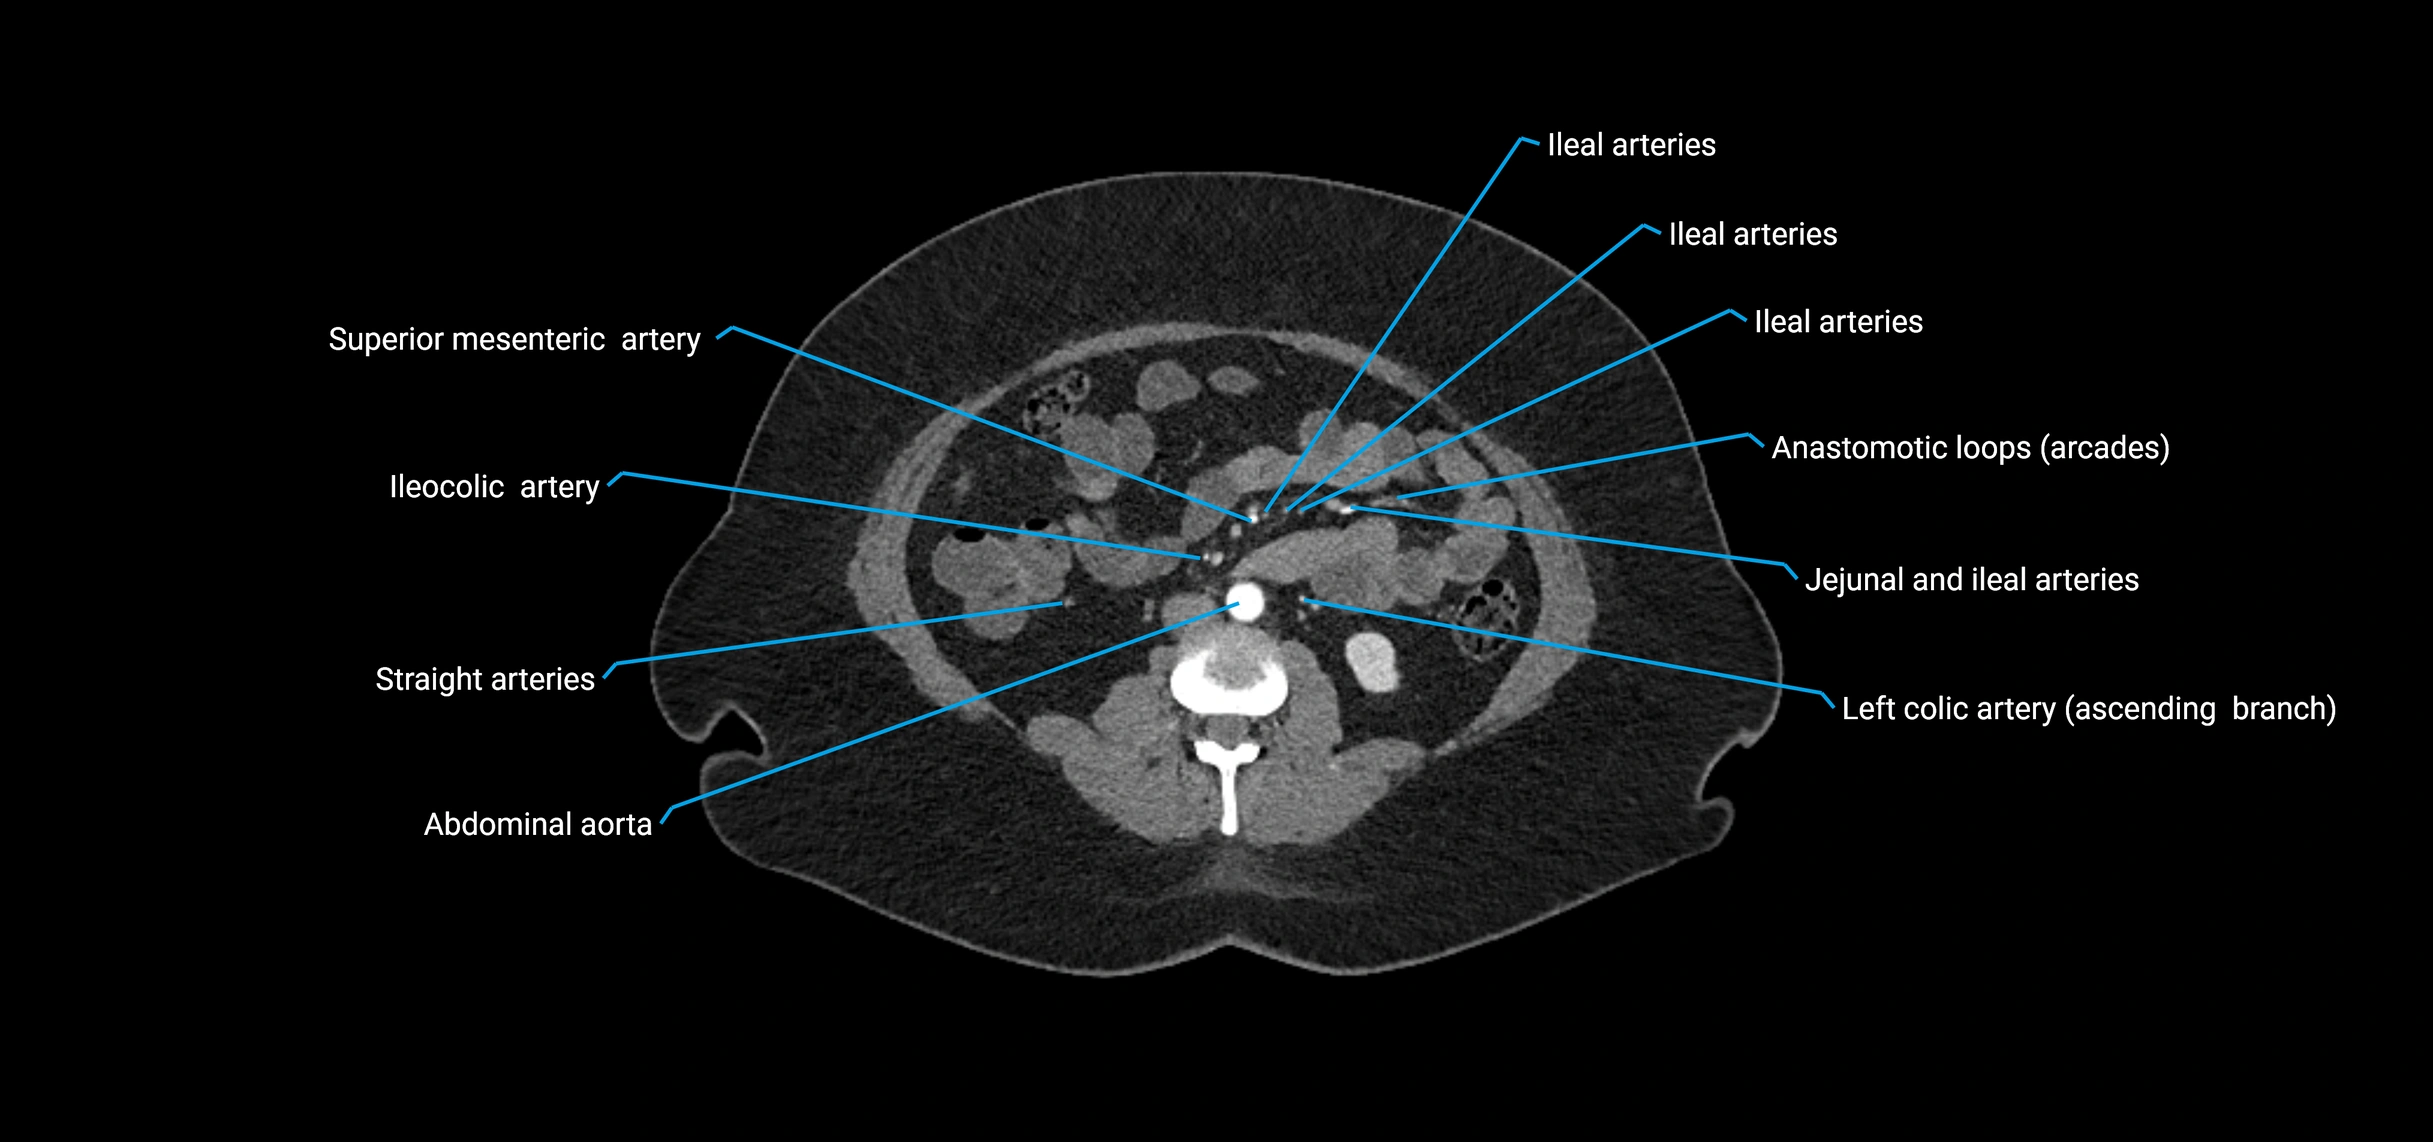

Contrast-enhanced CT (CTA):

• Gold standard for abdominal aortic imaging

• Provides excellent detail of lumen, wall, aneurysm, thrombus, and branch vessels

• Multiplanar and 3D reconstructions help in aneurysm measurement, stent graft planning, and dissection evaluation

• Detects acute rupture, traumatic injury, or occlusion with high sensitivity